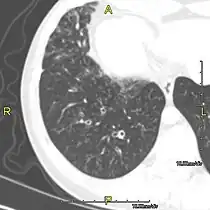

Around 80% of people with primary ciliary dyskinesia experience respiratory problems beginning within a day of birth. Many have a collapsed lobe of the lung and blood oxygen low enough to require treatment with supplemental oxygen.[3] Within the first few months of life, most develop a chronic mucus-producing cough and runny nose.[3] The main consequence of impaired ciliary function is reduced or absent mucus clearance from the lungs, and susceptibility to chronic recurrent respiratory infections, including sinusitis, bronchitis, pneumonia, and otitis media. Progressive damage to the respiratory system is common, including progressive bronchiectasis beginning in early childhood, and sinus disease (sometimes becoming severe in adults). However, diagnosis is often missed early in life despite the characteristic signs and symptoms.[4] In males, immotility of sperm can lead to infertility, although conception remains possible through the use of in vitro fertilization, there also are reported cases where sperm were able to move.[5] Trials have also shown that there is a marked reduction in fertility in females with Kartagener's syndrome due to dysfunction of the oviductal cilia.[6]

Many affected individuals experience hearing loss and show symptoms of otitis media which demonstrates variable responsiveness to the insertion of myringotomy tubes or grommets. Some patients have a poor sense of smell, which is believed to accompany high mucus production in the sinuses (although others report normal – or even acute – sensitivity to smell and taste). Clinical progression of the disease is variable, with lung transplantation required in severe cases. Susceptibility to infections can be drastically reduced by an early diagnosis. Treatment with various chest physiotherapy techniques has been observed to reduce the incidence of lung infection and to slow the progression of bronchiectasis dramatically. Aggressive treatment of sinus disease beginning at an early age is believed to slow long-term sinus damage (although this has not yet been adequately documented). Aggressive measures to enhance clearance of mucus, prevent respiratory infections, and treat bacterial superinfections have been observed to slow lung-disease progression. The predicted incidence is 1 in approximately 7500.[7]